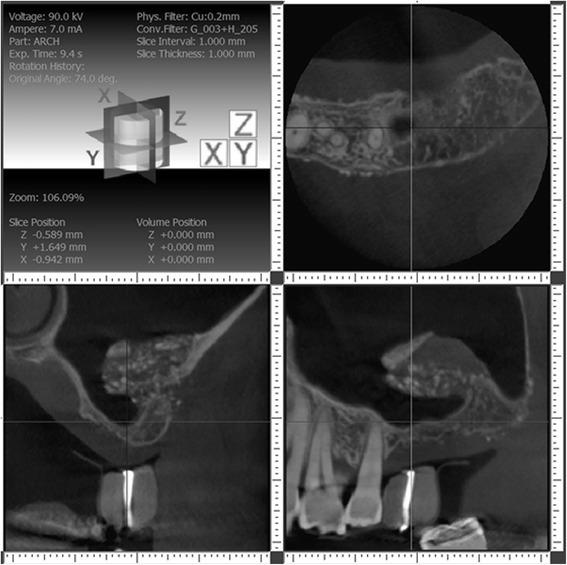

Patients with resorbed edentulous alveolar ridges in the posterior maxilla often require lateral window sinus augmentation procedures prior to implant placement. Lateral window sinus augmentation procedures can produce incomplete bone augmentation as consequence of surgical and healing complications producing unusual and complex sinus anatomy. Although incomplete bone formation after sinus augmentation has been described in a previous case reports, this is the first case report that describes grafting these compromised sites prior to implant placement.

A 65-year-old male patient with no known medical conditions presented with severe chronic localized periodontitis and a combined periodontal-endodontic lesion affecting three first molars. Initial ridge preservation and lateral window sinus augmentation resulted in incomplete bone formation and complex sinus floor anatomy on both right and left sides. A dilating balloon technique on one side and a palatal approach on the other side were utilized for additional sinus augmentation using particulate allograft and resorbable collagen membranes. Healing was uneventful, and implants could be placed and restored at all sites. Periodontal maintenance was conducted every 3 months, and the implants have been in function and periodontally healthy for 2 years.